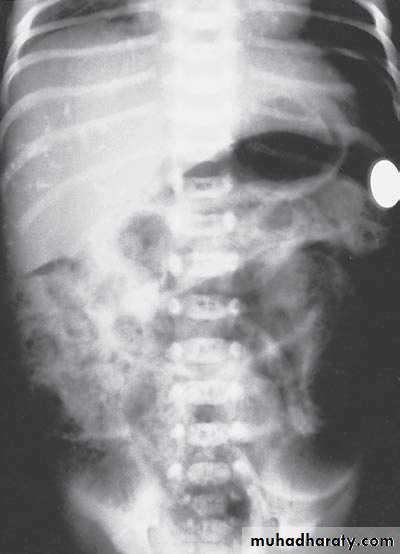

Bowel Obstruction

web